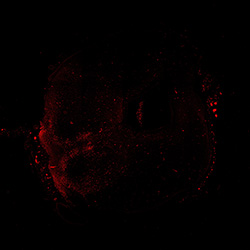

TH

6PCW human midbrain